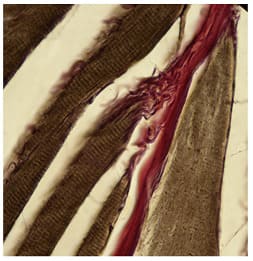

Histological specimens show that the tendons loose their mass as they go along the muscle belly (Figure 3). That is due to the fact that tendinous fibers detach from the tendon and without any junction cover the whole myofiber as loose connective tissue (Figures 4,5).

The only way the myofiber attaches to tendinous system is a parietal myotendinous junction (PMTJ) (Figures 5,6,7).

It is also clear that the tendinous system (tendons, endomysium and perimysium) is a continuous structure with no junctions. It is important to notice that the tendinous system is the structure that tears first in stretch-type injuries therefore one should follow the tendinous system to detect a tear. Ultrasound is a method of choice in this type of diagnostics. It only takes some effort to learn all the muscles tendinous systems anatomy. The end (cone) of the myofiber shows interesting feature of the tendinous system. At the level of the cone longitudinal striations can be seen on longitudinal/oblique sections (Figures 8,9,10). This phenomenon can be explained in only one way. This is where the loose connective tissue covering the whole myofiber must compress to single fibers of compact connective tissue and further on the tendon. It looks as they compress forming thin bands of tendon which gradually become a solid tendon. Therefore the end of the myofiber (the cone) is a transition zone from loose to compact connective tissue. At the cone level despite the parietal myotendinous junction there is another myotendinous junction mechanism. Actin filaments are anchored from one side to the Z-membrane, from the other side instead of interlacing with miosin penetrate through sarkolemma to the extracelular matrix just like integrines - also a parietal MTJ. Transverse sections of the muscle show that bands of endomysium are every few myofibers strengthened by bands of perimysium (Figures 11,12).